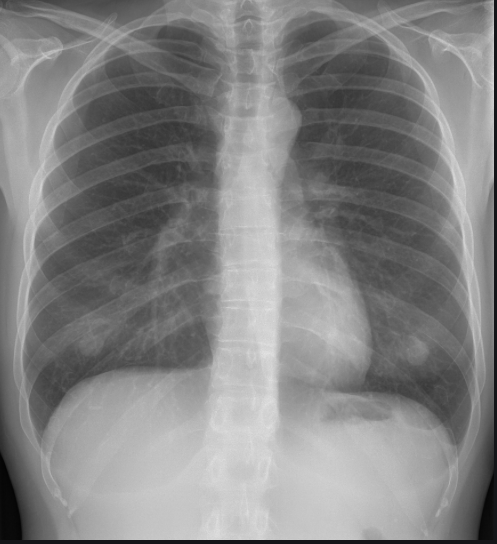

Identify the following anatomical structures

How do you systematically review a chest x-ray?